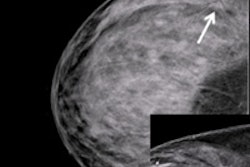

Nearly 300,000 women will be diagnosed with breast cancer and 40,000 will die from it this year, Harris wrote. But the data doesn't show that screening is the answer: Several studies, including the recent and highly publicized update of the Canadian National Breast Screening Study (CNBSS), highlight the danger of tying all our hopes to screening as a solution for the burden of breast cancer.

"Some researchers are framing it this way: If the current screening test doesn't work, we need to find another one -- like tomosynthesis or MRI," Harris told AuntMinnie.com. "I'm not saying these things shouldn't be investigated, but then again, if you start screening with a more sensitive test, you may reduce the number of women dying by a little bit, but you'll almost certainly increase overdiagnosis by a lot. We shouldn't pin all our hopes on screening, but rather expand our efforts to improve treatment and women's lifestyles. This back-and-forth about screening mammography just isn't getting us anywhere."